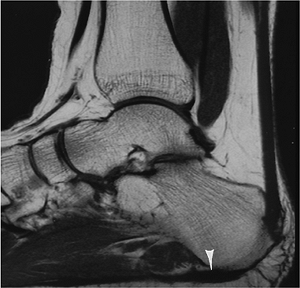

Infection: Diabetic Foot

-

Diabetic foot disorders result in more hospitalizations than other diabetic complications.

Up to 6% of diabetic persons undergo amputation because of infection and/or ischemic disease.

Ulcerations tend to occur over pressure

points (heel, metatarsal heads, tips of toes) on the foot. More than

90% of cases of osteomyelitis in the diabetic foot result from

contiguous spread from infected ulcers. -

Infection may be difficult to differentiate from neurotrophic arthropathy, especially the atrophic or osteopenic type.

![]() |

|

FIGURE 6-82 Diabetic patient with heel ulcer (open arrow) and abnormal signal intensity in the calcaneus caused by osteomyelitis.